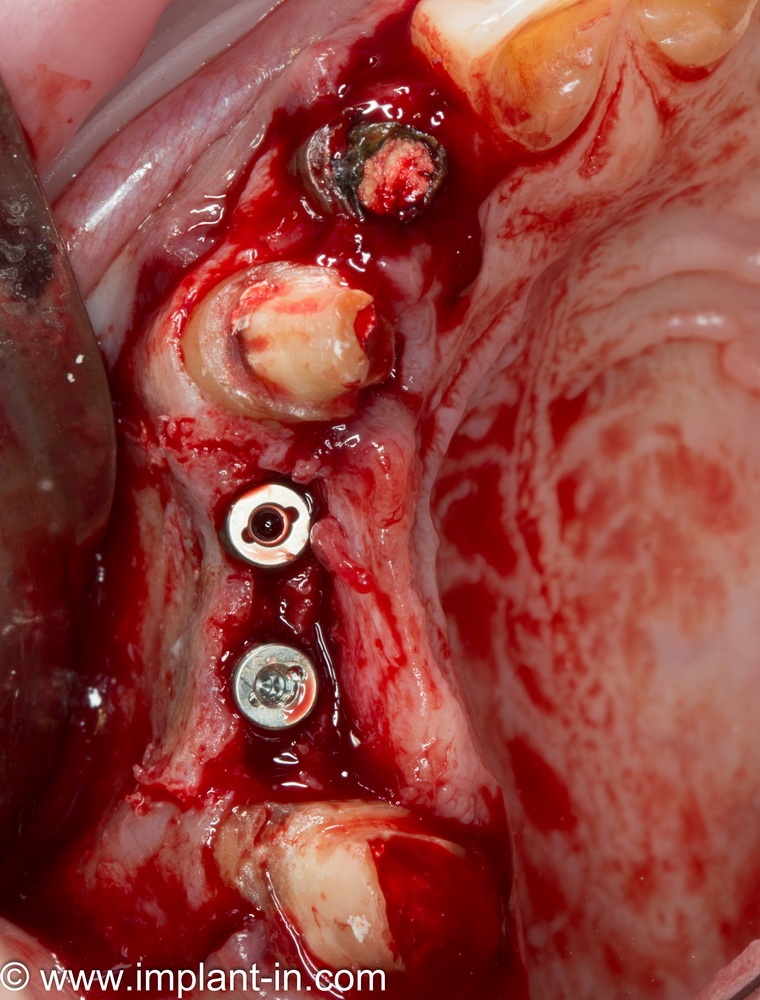

Я зафиксировал костный блок практически без адаптации на несколько винтов. Обрати внимание, что винты находятся в зоне, где не планируется установка имплантатов. Фиксация должна быть надежной, поскольку мне еще предстояла подготовка лунок для имплантатов. Трех винтов для этого вполне достаточно.

Дальнейшая адаптация костного блока свелась к сглаживанию острых краев. После чего я приступил к подготовке лунок и установке имплантатов.

Установка имплантатов.

Напомню, что для этой работы я выбрал субкрестальные имплантаты Ankylos C/X. Они прекрасно сочетаются с любым методом остеопластики.

Глянем на то, что получилось:

Осталось адаптировать костный блок (убрать острые края), проверить его фиксацию и, при необходимости, добавить винты. Десятисекундное дело.